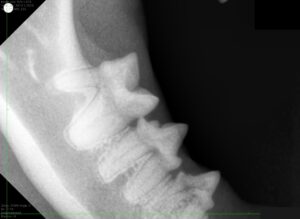

麻酔をかけた状態で、歯科レントゲン撮影を行い表からは見えない歯の根や歯の内部に異常がないかまで確認します。また、歯を1本ずつ触り歯周病によって歯周ポケットができていないか、出血がないかなども確認します。

歯科レントゲンにより、溶けている歯は1本だけであり歯根と顎の骨の癒着も少ないことがわかりました。